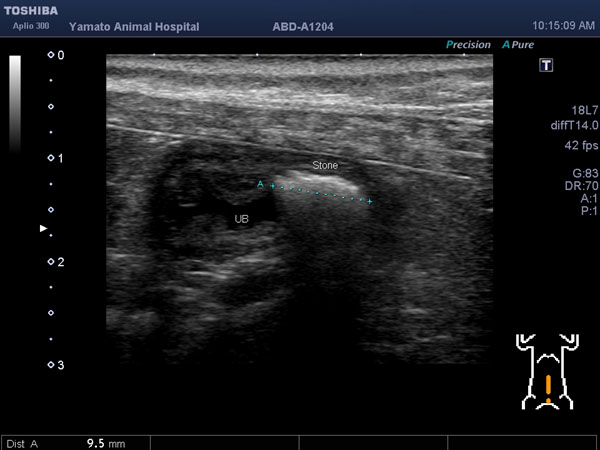

5~6歳以上の去勢手術をしていないオス犬に多い病気ですが、メス犬や去勢した犬に起こることもあります。お尻の筋肉が萎縮した結果、筋肉の隙間から直腸や膀胱が皮膚の下にとびでてしまいます。これにより便が出にくくなったり膀胱炎になったりします。手術をすることで機能回復および今後の致死的な状況を回避することができます。当院では去勢手術→結腸固定→前立腺固定→骨盤隔膜構成筋の縫縮→内閉鎖筋フラップ→浅臀筋フラップの順で通常腹側・臀部左右両側同時に行います。また老化以外に、筋肉が萎縮する原因があったり、腹圧がかかる原因があったりする場合も多いので、再発防止のためそれらの診断・治療も重要です。今回のワンちゃんも無事手術も終わり元気に退院しました。よかったね。